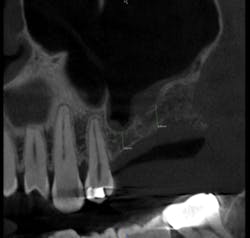

After reviewing the image, we performed a sinus lift procedure and placed two implant fixtures. A follow-up CBCT volume was taken one month later to check for overall healing, graft containment and sinus health (figs. 4, 5). The scan demonstrated normal healing from all perspectives. The patient went on to have the implants successfully restored once integration was clinically confirmed.

Figure 4:

Figure 5: